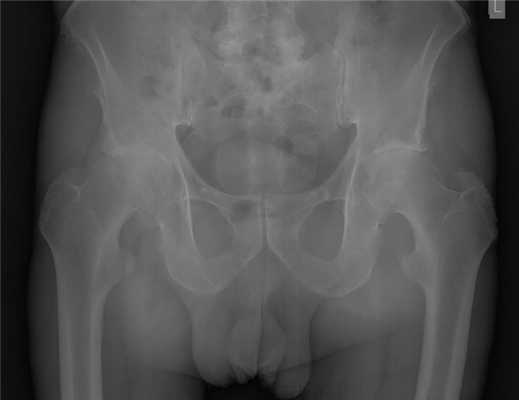

Пациент П. 64 лет на протяжении 3 лет отмечает выраженные, постепенно прогрессирующие боли в области правого тазобедренного сустава. Обратился в К+31 в мае 2017, осмотрен ортопедом, выполнены рентгенограммы тазобедренных суставов. Диагностирован коксартроз справа 3 ст, слева 2 ст. Рекомендовано оперативное лечение - тотальное эндопротезирование правого тазобедренного сустава.

Учитывая возраст пациента решено использовать протез бесцементной фиксации фирмы Zimmer, пара трения керамика\керамика.

Произведено предоперационное планирование, рассчётные размеры: ножка Avenir 6, чаша Trilogy 60, керамический вкладыш с внутренним диаметром 40 мм, керамическая головка 40 мм.